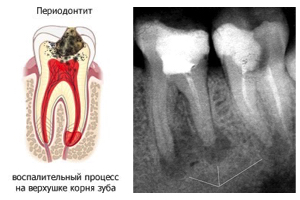

Периодонтит — воспаление тканей, которые окружают корень зуба и удерживают его в лунке.

Лечение производится в несколько этапов. Количество посещений и тактика лечения определяются индивидуально. Главной целью является ликвидировать очаг воспаления и удалить всю патогенную микрофлору на всех участках воспаления. В начале проводится диагностический рентгеновский снимок, либо компьютерная томограмма. Затем доступ к каналам зуба - снятие старой пломбы либо препарирование кариозной полости. Затем удаляются неркотизированные ткани, вся патогенная микрофлора, проводится тщательная инструментальная и антисептическая обработка. В канал вносится препарат кальция на срок от 2 недель до нескольких месяцев. После каналы пломбируются и герметично закрывается зуб. После лечения по истечение определённого срока проводится рентгенологический контроль лечения.